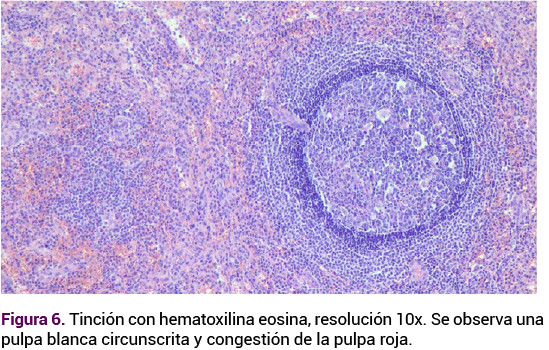

<strong>Figura 6</strong>

Figura 6. Tinción con hematoxilina eosina, resolución 10x. Se observa una pulpa blanca circunscrita y congestión de la pulpa roja.